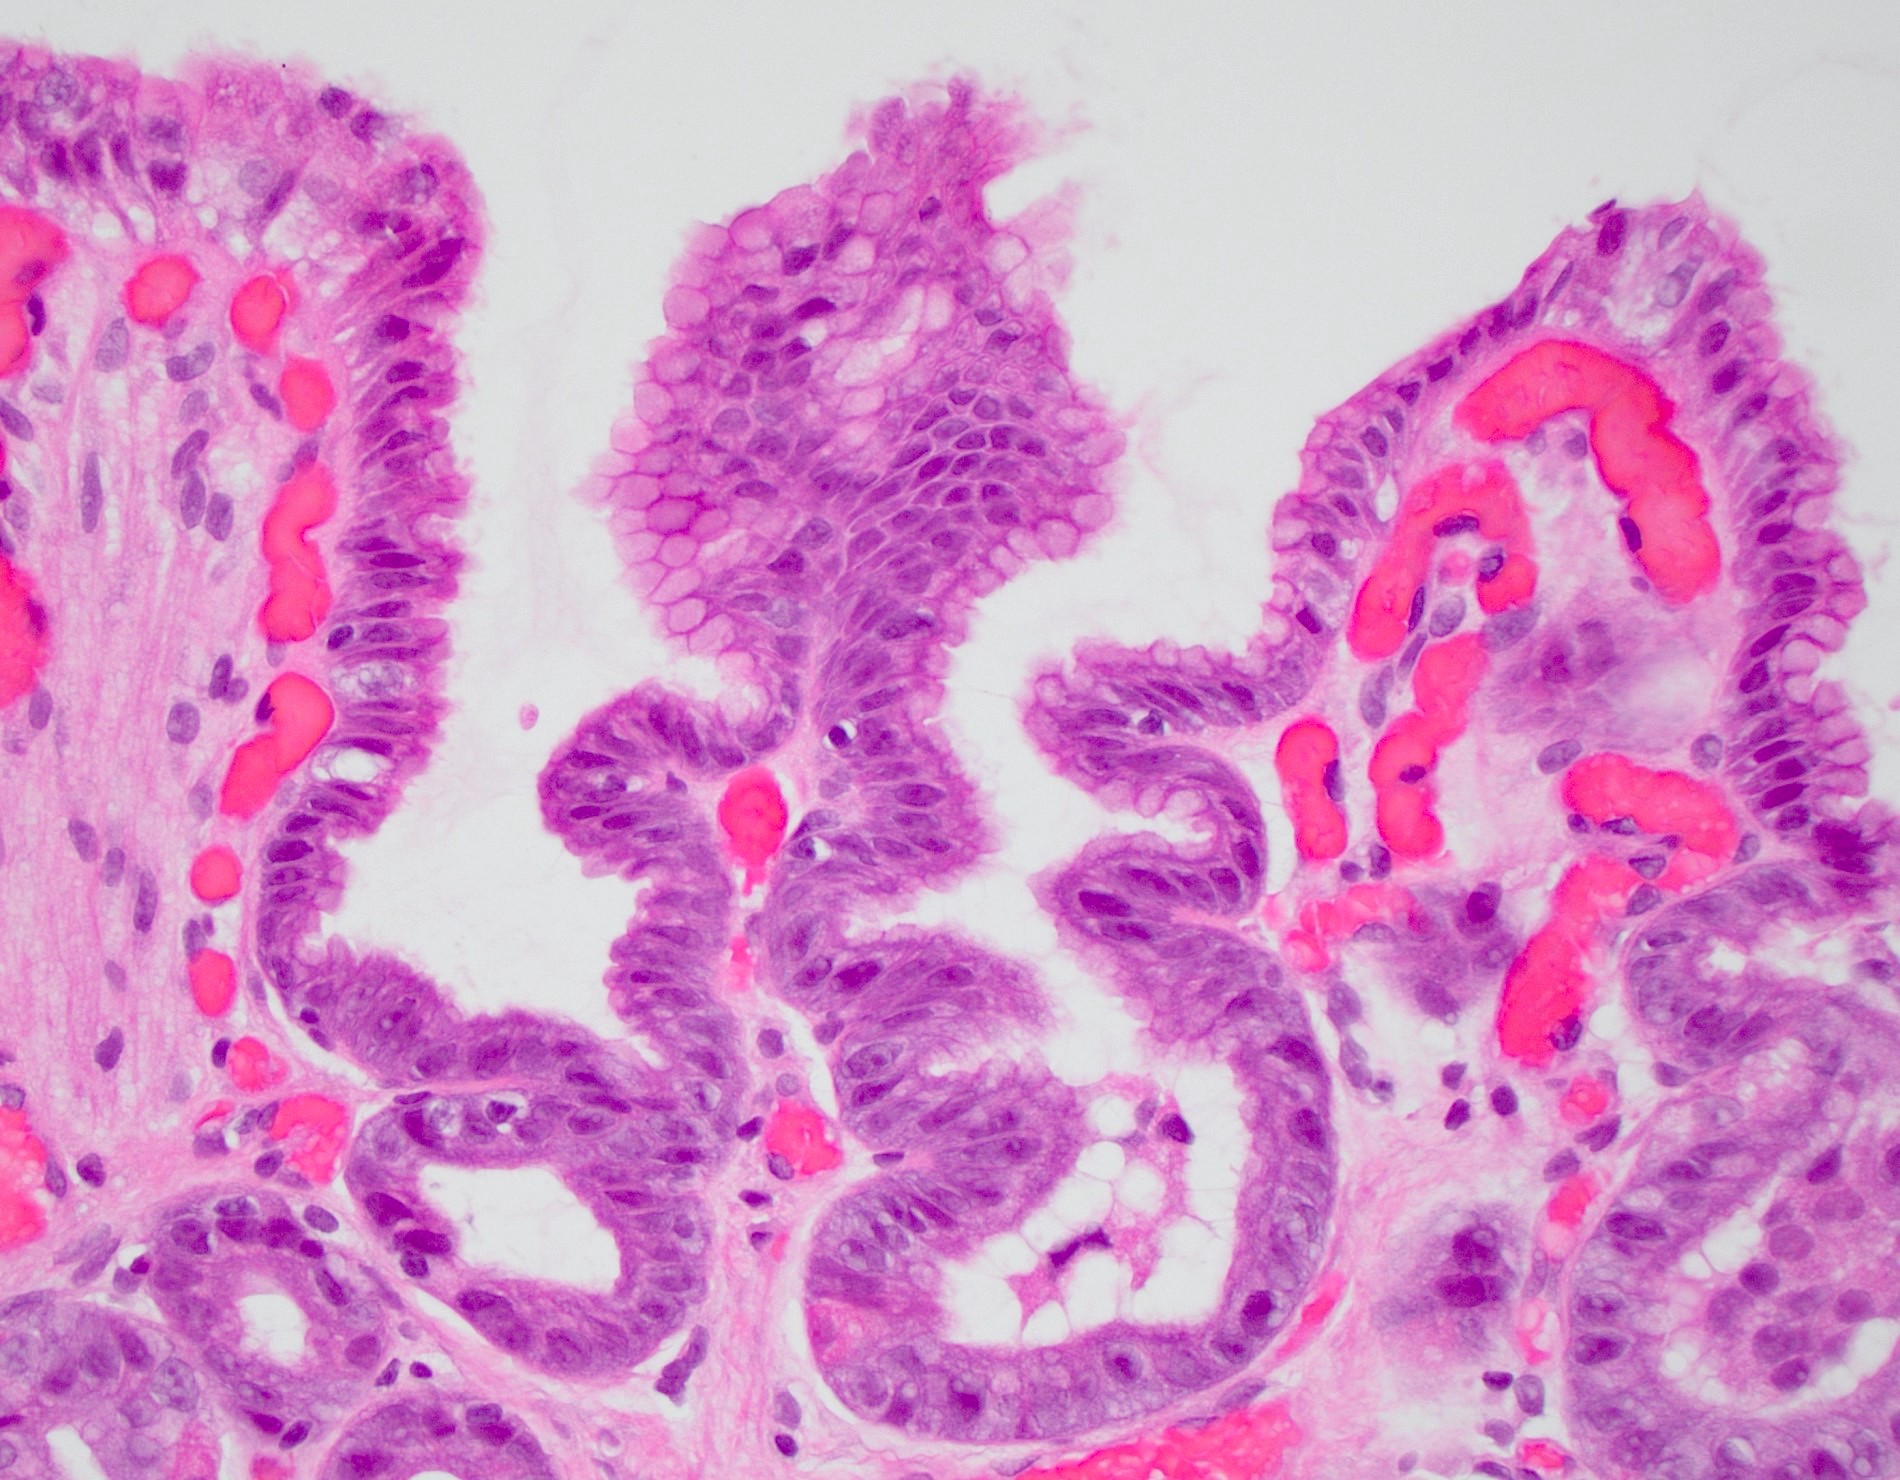

- Histology is characterized by foveolar hyperplasia, mucin depletion in surface epithelial cells and lamina propria expansion by fibromuscular and capillary hyperplasia

Microscopic (histologic) description

- Lack of significant edema or inflammation

- Foveolar hyperplasia: tortuosity / corkscrew appearance with a minimum twofold elongation of gastric cardiac foveolae and pits

- Mucin poor columnar cells with enlarged, hyperchromatic nuclei

- Lamina propria expansion with fibromuscular proliferation and congested, ectatic capillaries

Microscopic (histologic) images

A 48 year old woman with rheumatoid arthritis presents with dyspepsia and bloating. Endoscopy shows erythematous mucosa. Histopathology is significant for serrated gastric pits, foveolar hyperplasia, paucity of mucin in surface epithelial cells and ectatic superficial capillaries (see image). What is the diagnosis?

D. Reactive gastropathy. Histology of low grade dysplasia includes intestinal metaplasia, mucosal atrophy and pencillate, hyperchromatic nuclei within tall columnar epithelium. Gastric vascular ectasia will also have distended capillaries but with fibrin thrombi and without foveolar hyperplasia. Histology of H. pylori gastritis should emphasize more inflammation, especially epithelial neutrophils and plasma cells in the lamina propria.